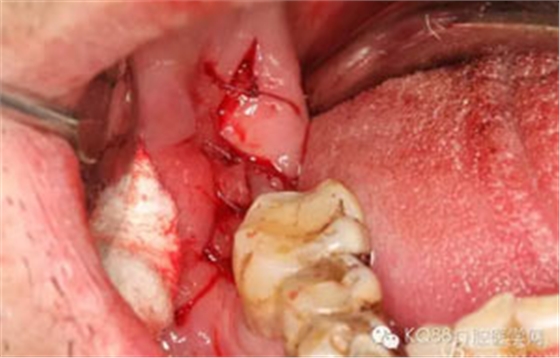

圖9.高速牙鉆分牙:

圖10.先頰舌向橫斷、然后再把牙冠近遠(yuǎn)中向縱分

圖11. “T”型的分牙。